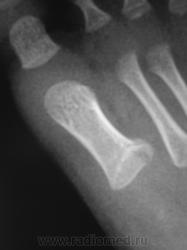

Насколько я разбираюсь в "детстве" ( а я в нем мало разбираюсь), вооружившись лупой( как обычно комп "виснет", я нервничаю),нашла краевой перелом основания 1 плюсневой кости.

Насколько я разбираюсь в "дестве" ( а я в нем мало разбираюсь), вооружившись лупой( как обычно комп "виснет", я нервничаю),нашла краевой перелом основания 1 плюсневой кости.

Перелом первой плюсневой, типичный перелом у маленьких детей.

Да, имела ввиду характер перелома, первая плюсневая всегда так ломается. А механизм травмы, практически, одинаков - запнулся. Если хотите, могу много таких перелом поискать на работе.

Думаю есть подвывих в проксимальном межфаланговом суставе 2-го пальца.

Вот еще один такой перелом (сегодня их было три), так что, довольно частый и характерный вид перелома.

"Частый". Это, по всей видимости, у Вас частый, у нас редкий. Я лично не вижу. Если не затруднит Вас, дама прекрасная, стрелочкой тыкните.

Да все как обычно, тыкнула ))))

Спасибо, увидел.

- если рентгенограмма одной стопы в двух проекциях, тогда одна красная стрелка обшибочна...

Ничего не ошибочно, это "ступенька" по тыльной поверхности.